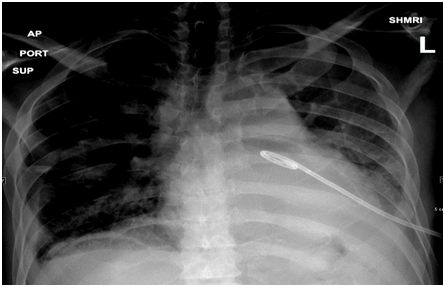

On initial examination, the patient was found to have borderline BP (SBP 101, DBP 60), diminished air entry at the bilateral right and left inferior lung fields. The cardiac examination was remarkable for normal S1, S2 and distended jugular venous distension of 10cm. Chest radiography (CXR) showed an intact esophageal stent along with radiolucent rim surrounding the cardiac silhouette (Figure 1). Echocardiogram (echo) revealed an air gap sign echoic dense space at the anterior and basal part of the heart consistent with the pneumopericardium with no signs of tamponade (Figure 2).  Computed tomography (CT) scan chest confirmed the presence of pneumopericardium in anterior pericardium along with left sided mediastinal pocket of air with foci of gas above the esophageal stent likely communicating with the pericardium (Figure 3). Given the clinical and radiological evidence of the symptomatic large pneumopericardium, we consented the patient on an emergency pericardiocentesis. Goals of care were discussed with the patient and his family and the patient opted interventional care measures. A following pericardiocentesis (with off label CT guidance) right sided parasternal approach (marked at the right 5th intercostal space with angulated entry projection of 70 degree medially with 27mm depth) was performed successfully with aspiration of 70ml of air followed with frothy blood-stained aspirate. The gentleman symptoms resolved immediately with picked up BP (SBP 123,DBP 67) and pigtail kept and secured in place for 5days without any complications.  Thereafter, a follow up echo and CT scan repeated and showed bright improvement in the clinical status (Figures 4 & 5) respectively.

Figure 4 CXR in supine position shows resolution of the radiolucent rim and peg tail in the place around the pericardium.